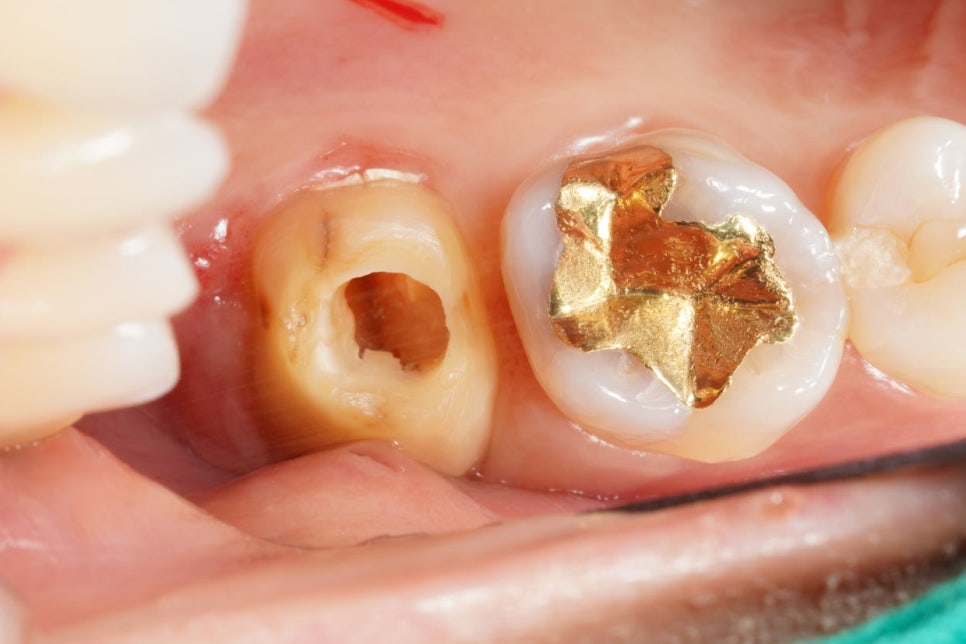

이전 치과에서 해놓은 AO가 좀 아쉽죠

치아 앞쪽을 너무 많이 파먹었습니다.

형태도 좀 아쉽네요

삼각형이 아니고 동그란 형태인 게.

근관도 안찾아놓으셨구

바쁜 치과였나봅니다.

미세한 신경관인 MB2는 없었습니다

다행히.